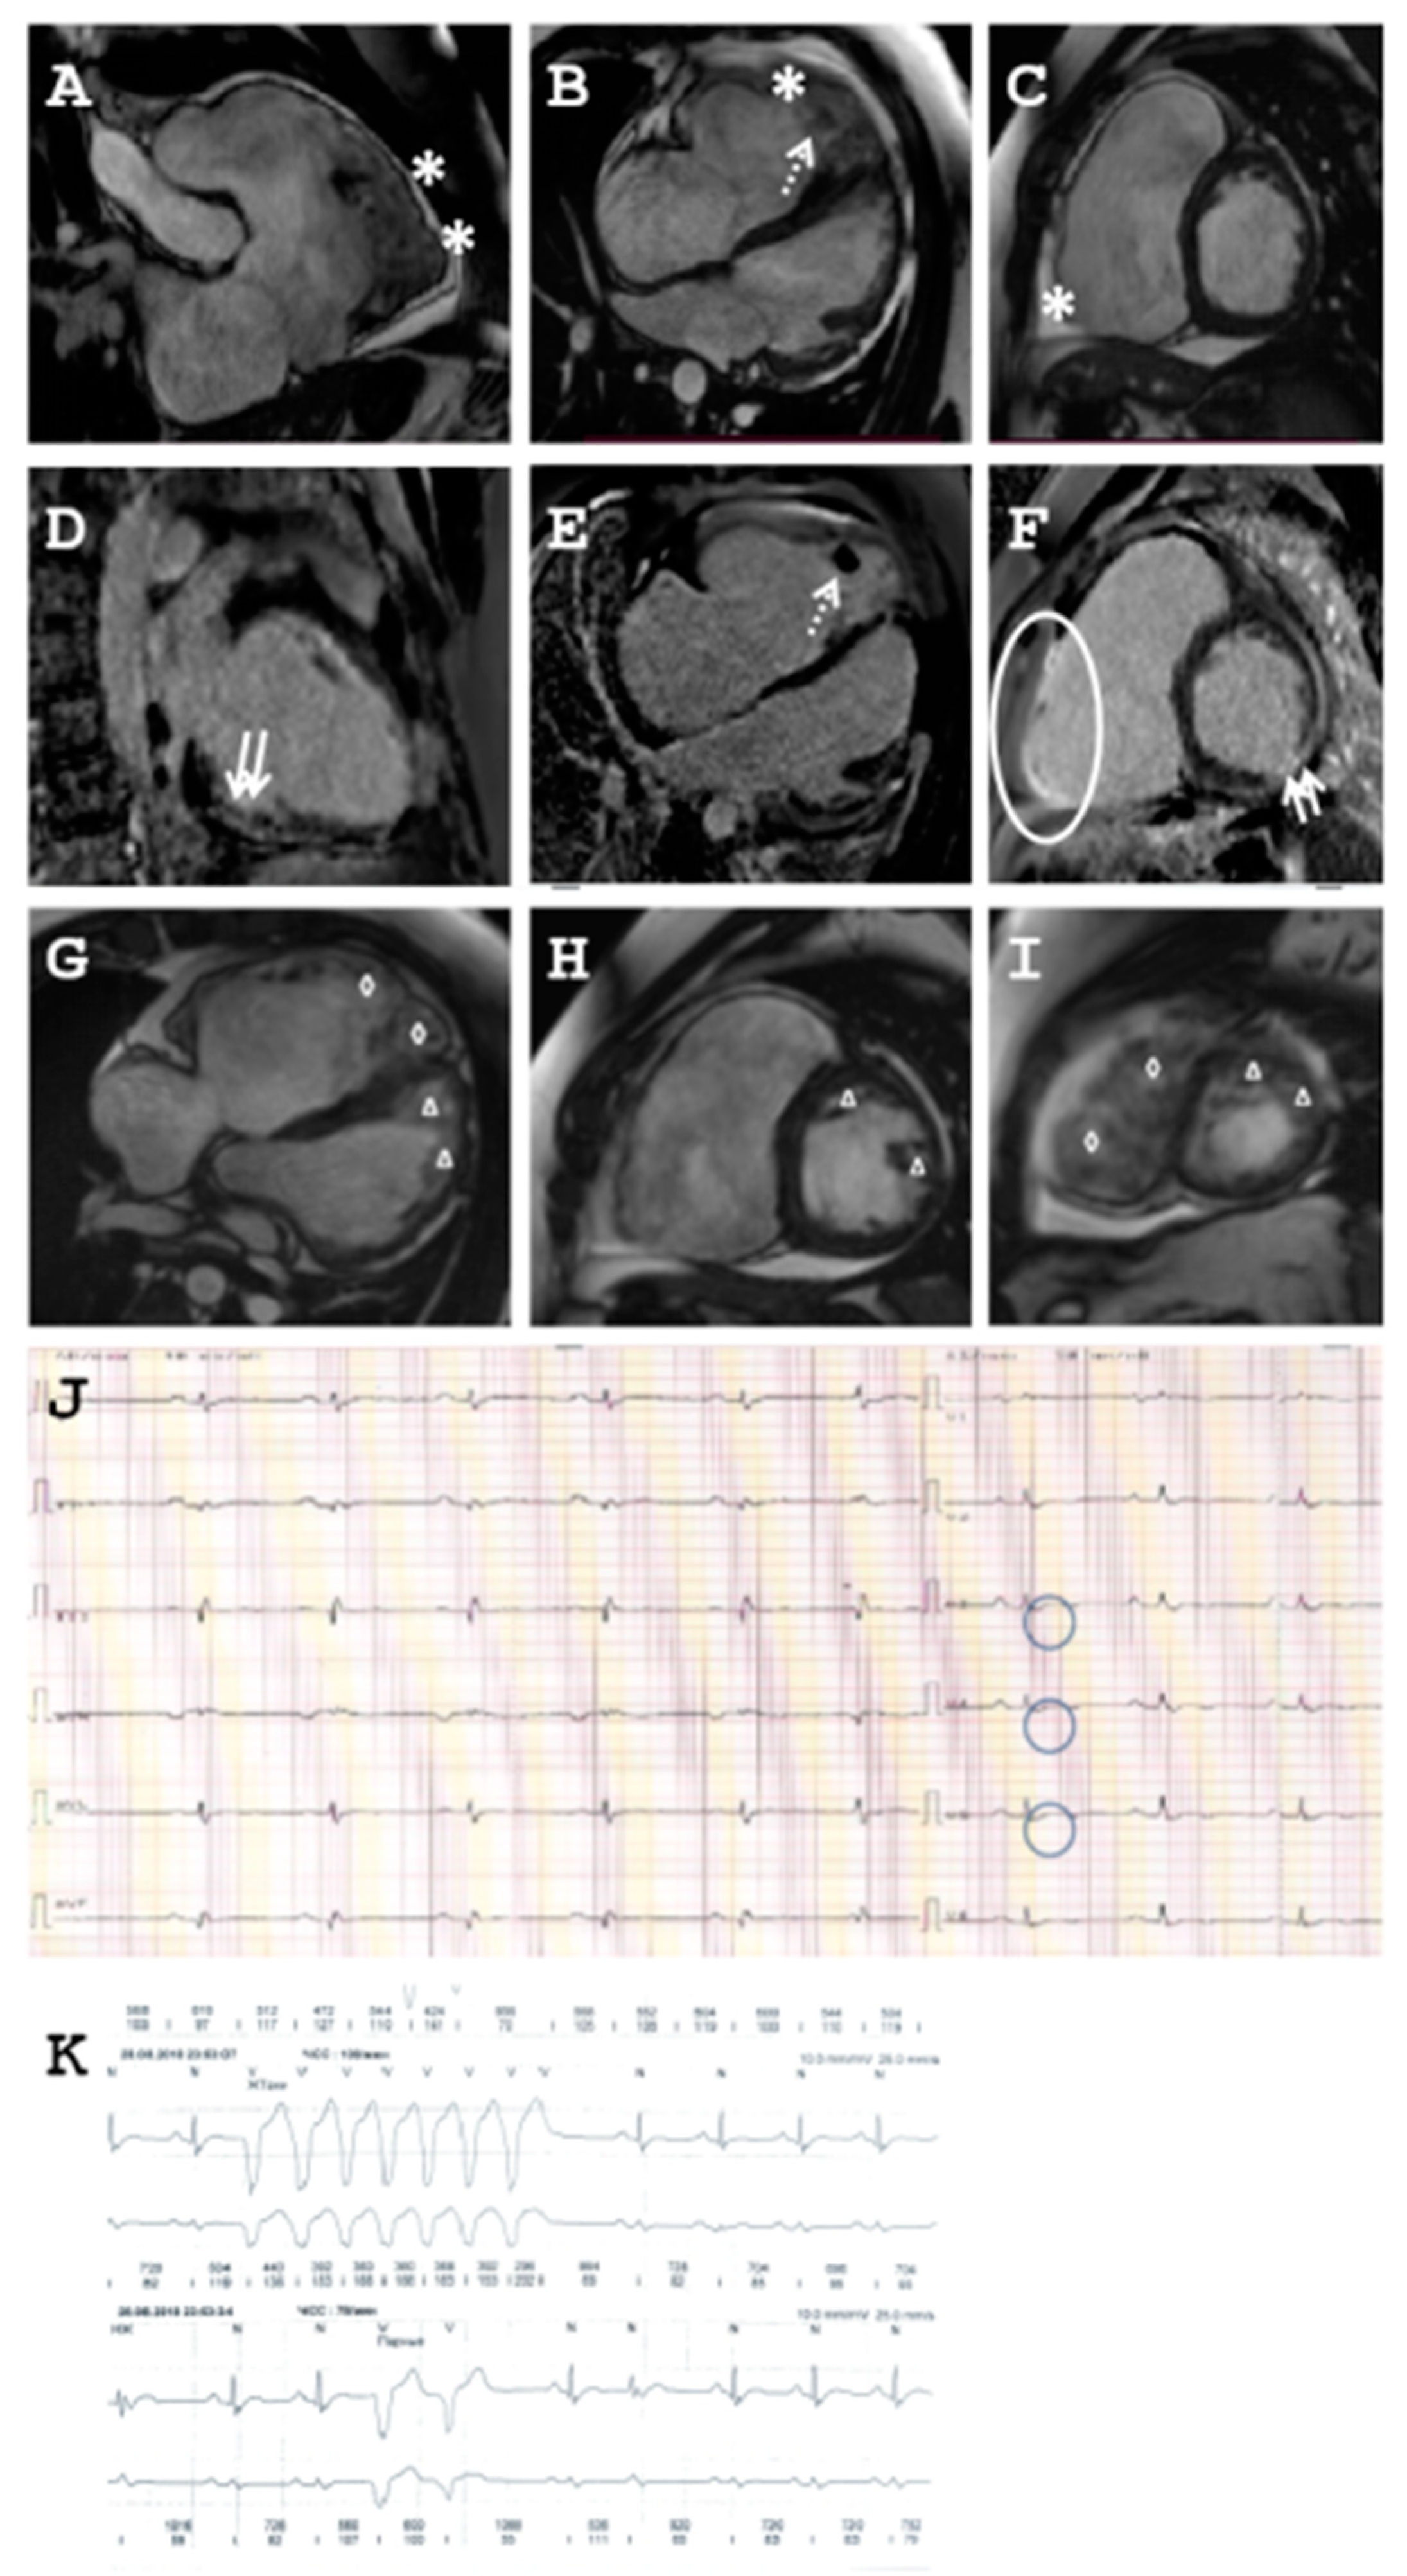

2.1.1. Family A

2.1.2. Family B